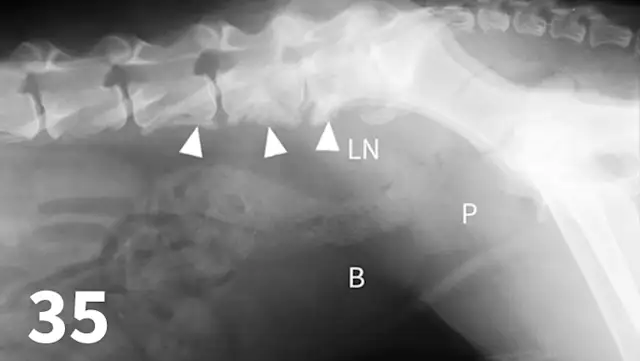

Survey radiography can be used to evaluate the size, shape, and opacity of the prostate gland (Figures 31 and 32). Ultrasonography has the advantage of providing tissue-architecture information. Prostatic abscesses, internal cysts, and paraprostatic cysts are readily visualized on ultrasonography. Ultrasonography can also aid in diagnosing benign hyperplasia (homogenous echotexture with intact capsule) and prostatic neoplasia (heterogenous with course echotexture and irregular margins) (Figure 33) and with identifying any potential source of excess androgen production (eg, adrenal glands, retained testes) in cases of suspected squamous metaplasia of the prostate gland. Mineralization of the prostate in a neutered dog is suggestive of neoplasia and can be detected by both survey radiography and ultrasonography. Sublumbar lymph nodes can also be evaluated by ultrasonography, whereas radiography is best for evaluating the adjacent lumbar spine (Figures 34 and 35).

Figure 31.

The prostate gland (arrows) in this intact male dog is enlarged but normal in shape with smooth margins and soft tissue opacity. Although this is consistent with benign prostatic hypertrophy, ultrasound would be useful to further define tissue architecture.